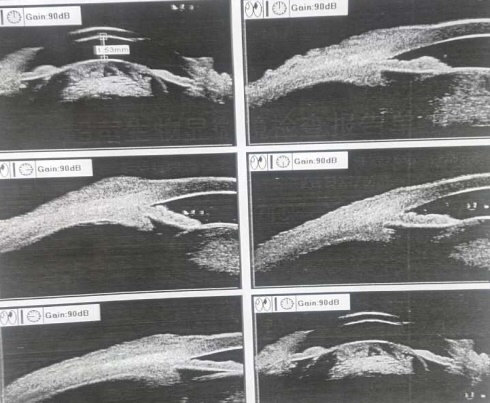

其实病因也基本一样,眼部检查图片如下

这就是典型的白内障未尽早治疗,“長(cháng)得过熟”,而继发青光眼的病例。再追问病史,也都会得到相似的答(dá)案,“早就知道有(yǒu)白内障,都说長(cháng)熟了才能(néng)做”,“電(diàn)视上说有(yǒu)药物(wù)能(néng)控制白内障,能(néng)不做手术就不做吧”等等。